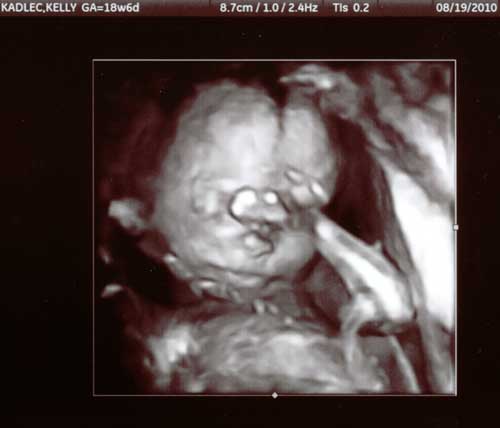

19 August 2010 |

At our 19 week ultrasound appointment,

he looks a little camera shy with his hand in front of his face